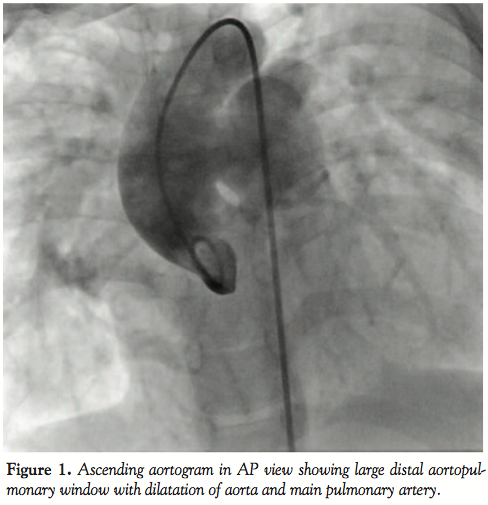

The child was taken up for assessment of PVR and device closure of the APW. The femoral artery and vein were percutaneously cannulated. Unfractionated heparin (100 units/kg) was administered after vascular access was obtained. There was a 20% increase in saturation at the left pulmonary arterial level compared to superior vena cava. She had high pulmonary artery pressures (76/44 mmHg, mean=55 mmHg, 2/3 of systemic pressures), Qp/Qs was 3.5:1 and PVRI was 6·1 Wood units·m2. Ascending aortography demonstrated a large distal APW measuring 14 mm. As the defect was about 6 mm away from coronary ostium, using an atrial septal occluder (which has a 7 mm rim) could have compromised the coronary opening so we decided to use a muscular VSD device. The defect was crossed antegradely from pulmonary artery and an extra stiff Amplatz (360 cm) wire (Cook Medical) was placed in the descending aorta. A 9 Fr long sheath (Cook) was tracked over the wire, across the APW, and was lodged into the descending aorta. An 18 mm muscular VSD device (ShenZhen) was introduced into the long sheath and the distal (left ventricular) disc was opened in the aorta. The device was then retracted towards the defect, and the proximal (right ventricular) disc was opened on the pulmonary arterial side of the defect. The mean PA pressure dropped to 36 mmHg. Appropriate device position was confirmed both by transthoracic echocardiography and angiograms in multiple views. There was no residual flow across and no obstruction to either aortic or pulmonary arterial flow. She was put on oral aspirin for 6 months and her 1-year follow-up showed improved physical growth, no obstruction to aortic or pulmonary arterial flow, and near normalization of PA pressures on 2D echocardiogram.